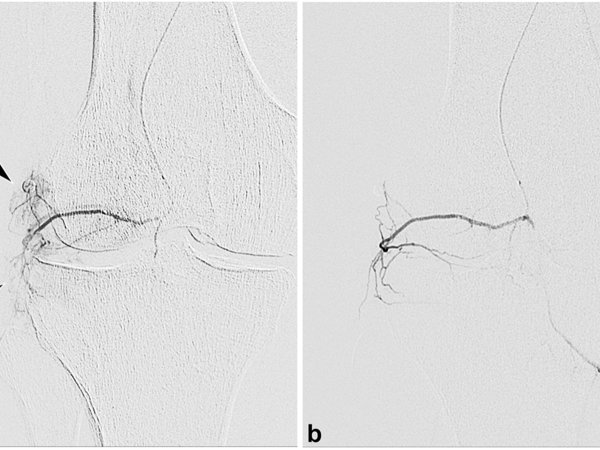

Cusumano, Lucas R. et al. Genicular Artery Embolization for Treatment of Symptomatic Knee Osteoarthritis: 2-Year Outcomes from a Prospective IDE Trial. JVIR. 2024;35(12):1768-1775

LC: GAE is gaining increasing acceptance as a treatment for knee osteoarthritis. However, the long-term data is limited specifically for this treatment. As a result, the focus of our study was to present the 2-year follow up data for our GAE patients. Our 1-year data was previously published by Siddharth A. Padia, MD, FSIR, in 2021 in the Journal of Bone and Joint Surgery. Two important features of our study that are worth noting is first, we used a relatively high bar for clinical success, which was at least a 50 percent decrease in Western Ontario and McMaster Universities Osteoarthritis Index (WOMAC) scores.

Second, we included patients with moderate to severe knee osteoarthritis judged on the Kellgren and Lawrence score that was two to four. We chose this because we thought it would more accurately represent the demographics seeking GAE treatments for pain relief for knee osteoarthritis.

LC: We found that the clinical outcomes after GAE were sustained for most patients at 2 years if they respond to initial treatment. Of the patients who responded at 12 months, 72% had durable response at 24 months and 28% had a relapse of symptoms. Of all the patients we treated, 47% demonstrated clinical success at 24 months and importantly, there were no long-term adverse events after GAE procedures.